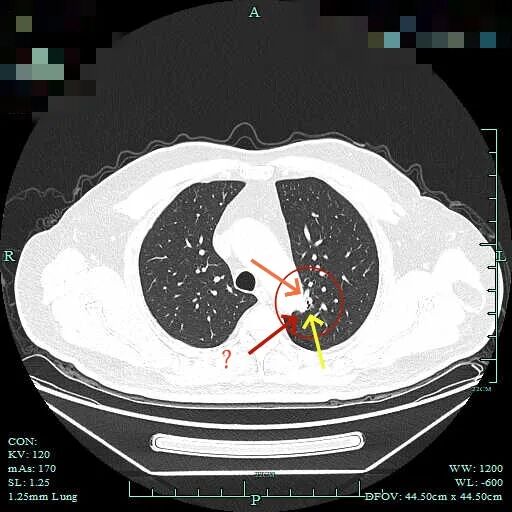

杭州市肿瘤医院影像展示与分析:

右上也有混合密度结节,实性部分缺乏膨胀性与收缩力,磨玻璃成分较淡,也偏糊,但持续存在仍得考虑肿瘤范畴可能性大。

此视角是混合密度,实性为主,贴胸膜近。